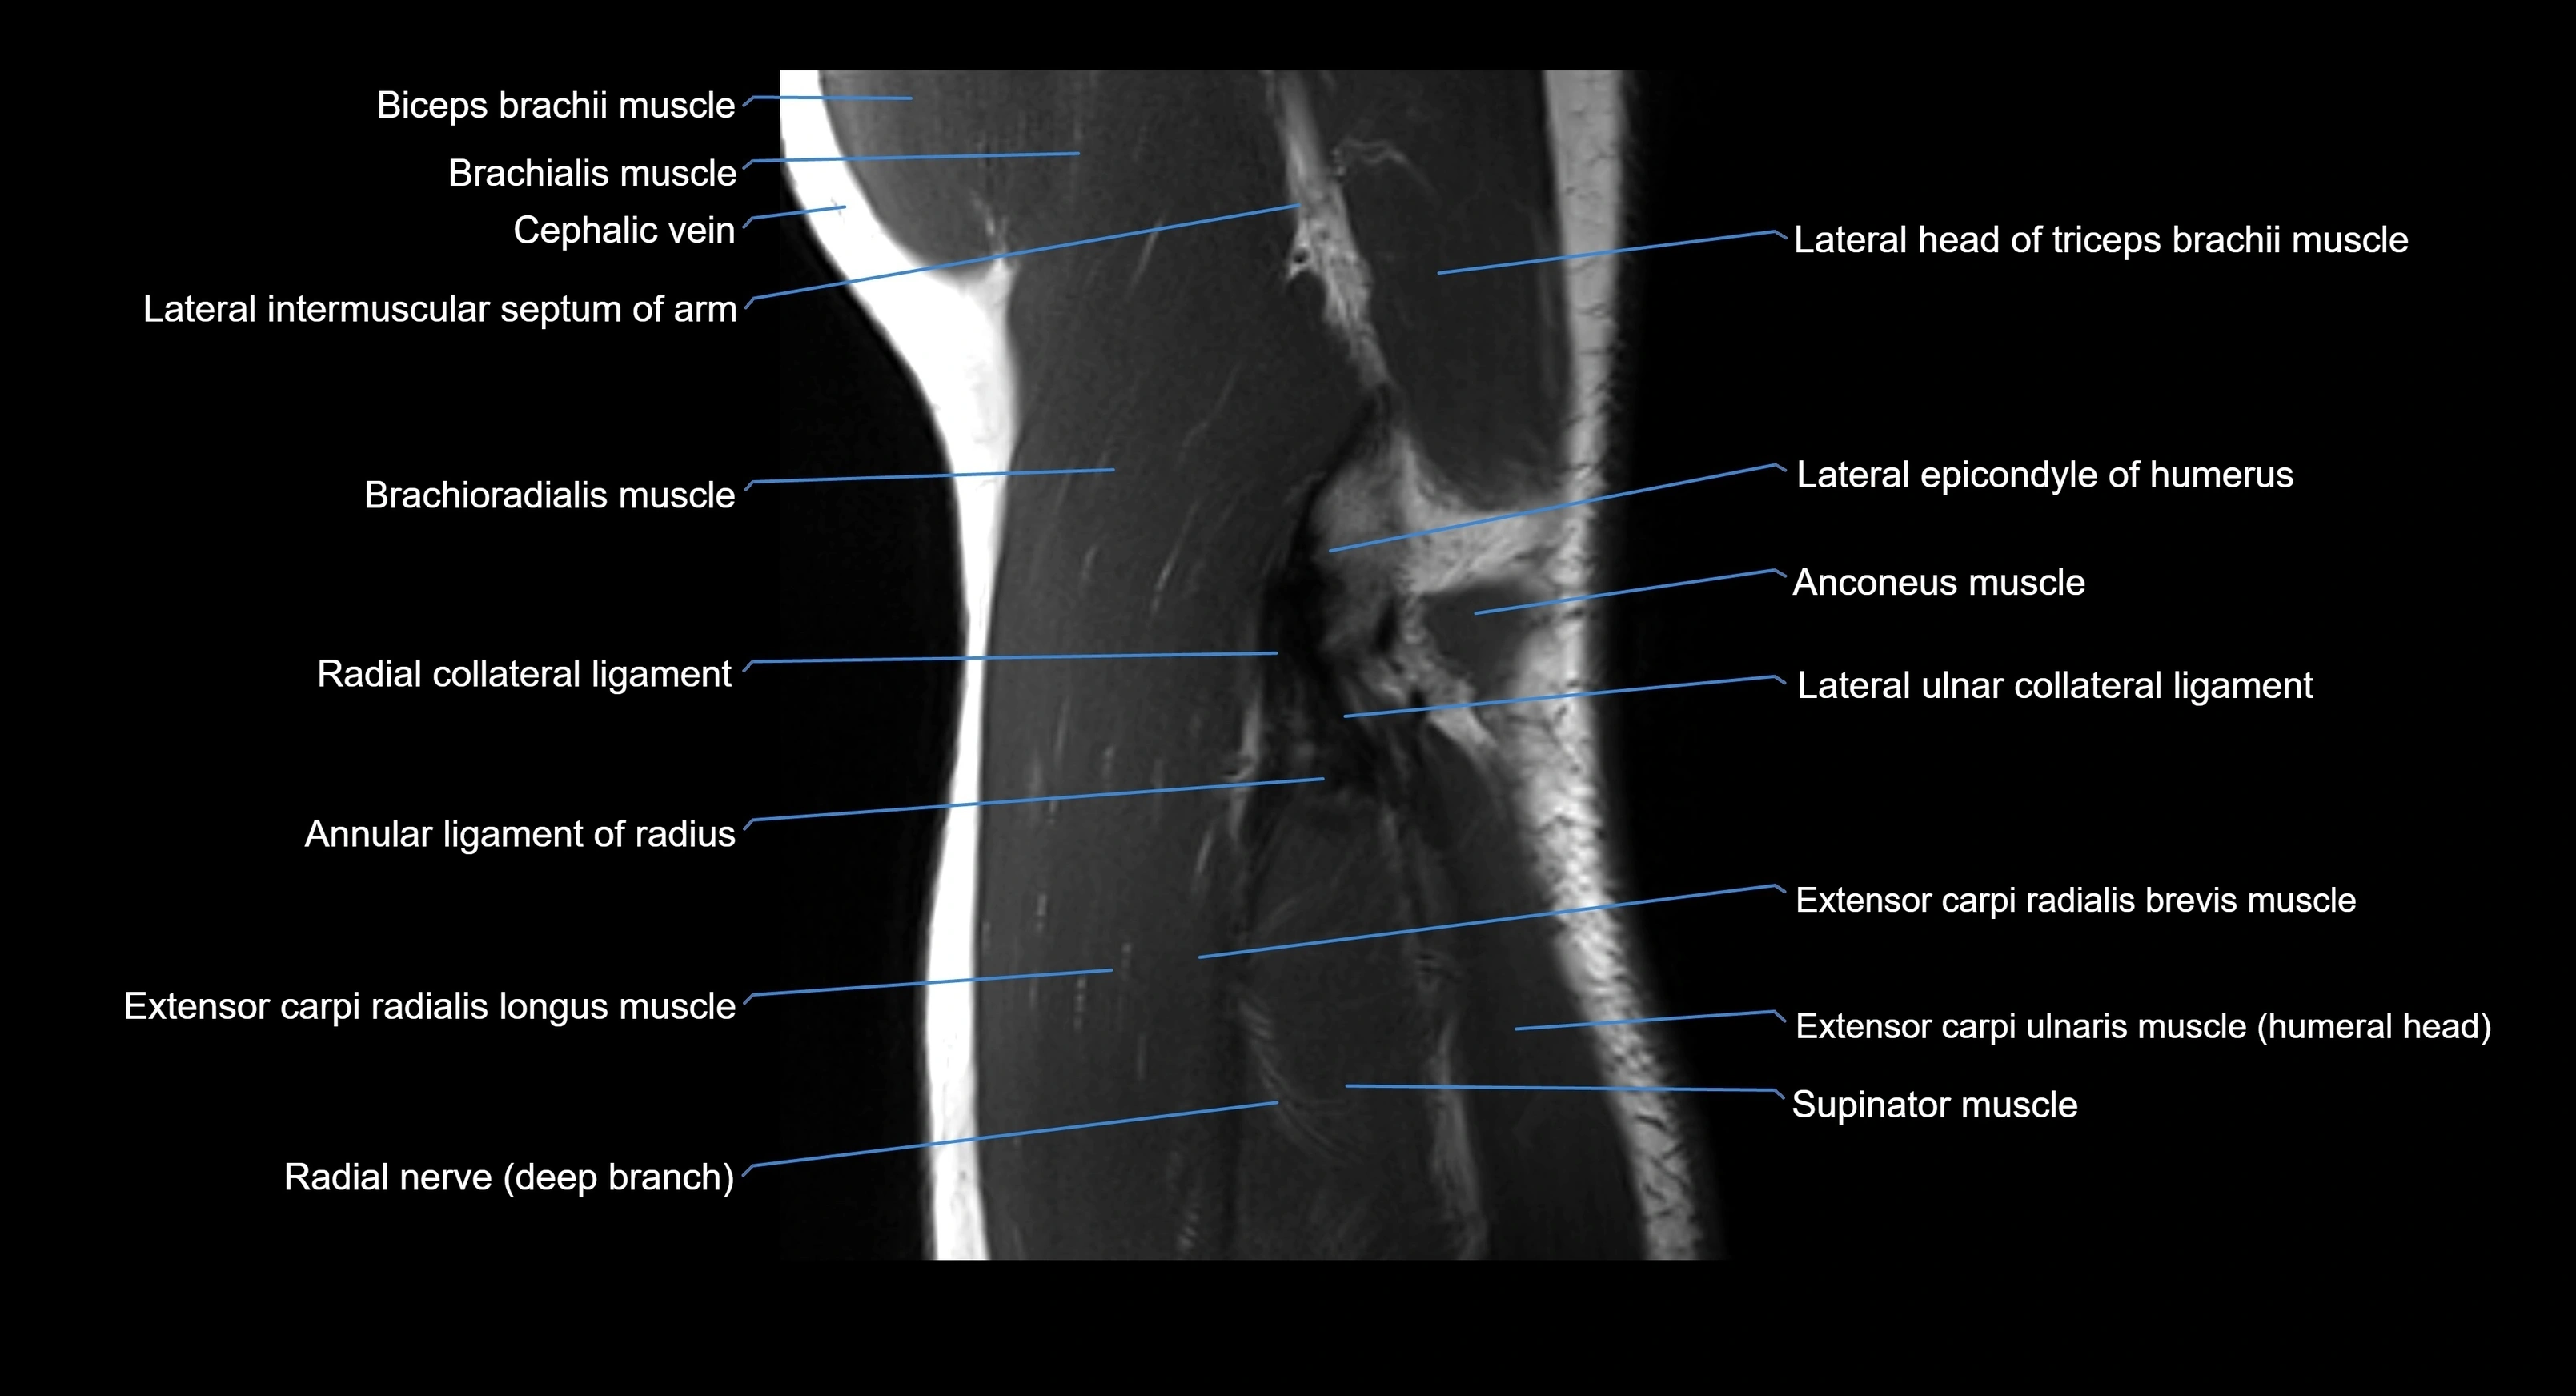

MRI image

image